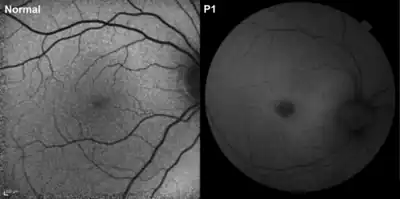

Because vision loss is often an early sign, NCL may be first suspected during an eye exam. An eye doctor can detect a loss of cells within the eye that occurs in the three childhood forms of NCL. However, because such cell loss occurs in other eye diseases, the disorder cannot be diagnosed by this sign alone. Often, an eye specialist or other physician who suspects NCL may refer the child to a neurologist, a doctor who specializes in disease of the brain and nervous system. To diagnose NCL, the neurologist needs the patient's medical history and information from various laboratory tests.